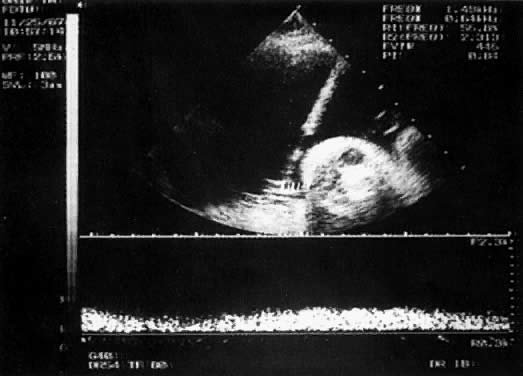

With the freehand technique, the transducer and needle are managed either by one person or by a team of two. If one is working alone, a second person is required to withdraw the sample or to inject through the needle. Because the needle direction can be readjusted laterally, many prefer the freehand to the needle-guided technique. With the needle-guided technique, the needle's travel is limited to one plane (Fig. 1). The needle tract is displayed on the ultrasound screen, permitting precise alignment of the tract with the vessel (Fig. 2).

Fig. 2. Needle-guided technique shows needle in umbilical vein confirmed with Doppler.